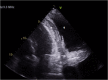

Pericardial effusion has a broad spectrum of clinical presentation, ranging from an incidental finding on imaging to a potentially fatal emergency such as pericardial tamponade, the most severe presentation. The authors present a case of a middle-aged male hospitalized due to shortness of breath. Initial work-up was positive for massive pericardial effusion with haemodynamic compromise. Additional study revealed panhypopituitarism. The acromegalic phenotype was suggestive of acromegaly secondary to pituitary adenoma, which had probably evolved to apoplexy. Hormone replacement was started with clinical improvement. At the 3-year follow-up, there was no evidence of recurrence of pericardial effusion. Panhypopituitarism is a relatively rare entity, but can lead to life-threatening complications such as adrenal crisis, coma and myxoedema-associated cardiac failure. Pericardial effusion is an extremely rare manifestation of secondary hypothyroidism.